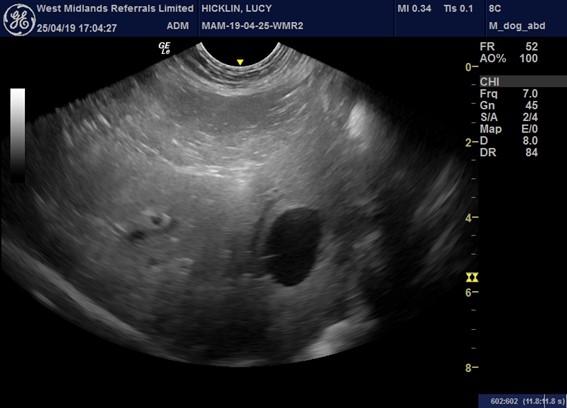

“An ultrasound scan identified the mass was approximately 1.5cm in diameter and in the right limb of the pancreas so we operated and carefully dissected the tumour.